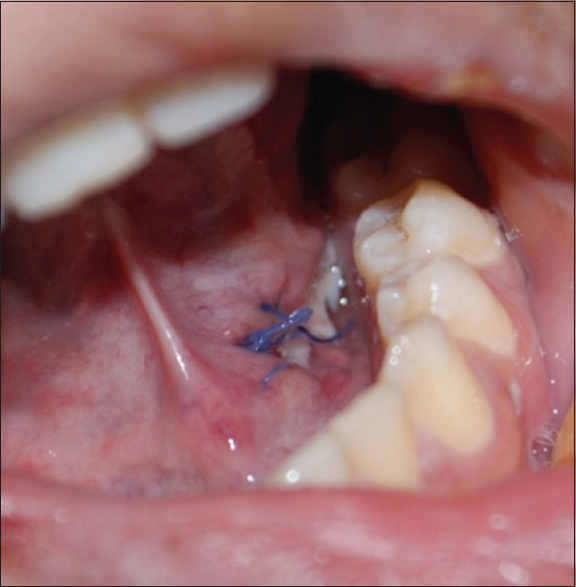

The major salivary glands (parotid, submandibular, and sublingual) are most frequently obstructed by calculi within the salivary gland, or more uncommonly, by ranulas. Despite the well-defined clinical and radiographic diagnostic features, sialolithiasis may sometimes be confused with sialadenitis and ranulas, especially when encountered in general dental practice. We, therefore, present a case that illustrates this diagnostic dilemma to highlight the salient features of all three conditions. A 28-year-old female presented with a history of a submandibular swelling for 8 months. On intraoral examination, a bluish sublingual swelling was identified at the left side of the lingual frenum, causing a slight elevation of the tongue. The preliminary diagnosis was of a ranula; however, the clinical history suggested sialolithiasis. A hard structure was palpated in the submandibular gland, and a mandibular occlusal film revealed a large ductal sialolith. Sialolithotomy was performed under local anesthesia, and a single 7.2 mm stone was retrieved. The postoperative follow-up period was uneventful, with good healing and restored normal salivary flow. Despite the fairly clear clinical and radiographic diagnostic criteria suggestive of sialolithiasis, the bluish-tinged swelling of the floor of the mouth prompted the examining dentist to provisionally diagnose a ranula. Sialolithiasis is a common obstructive condition of the salivary gland encountered in the dental setting. Despite the clinical and radiographic features usually guiding the correct diagnosis, it can be a challenging diagnosis for less experienced dentists, who must always carefully consider the history, clinical, and radiographic findings.